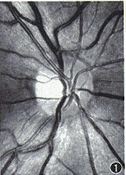

图1 正常清晰的RNFL图像